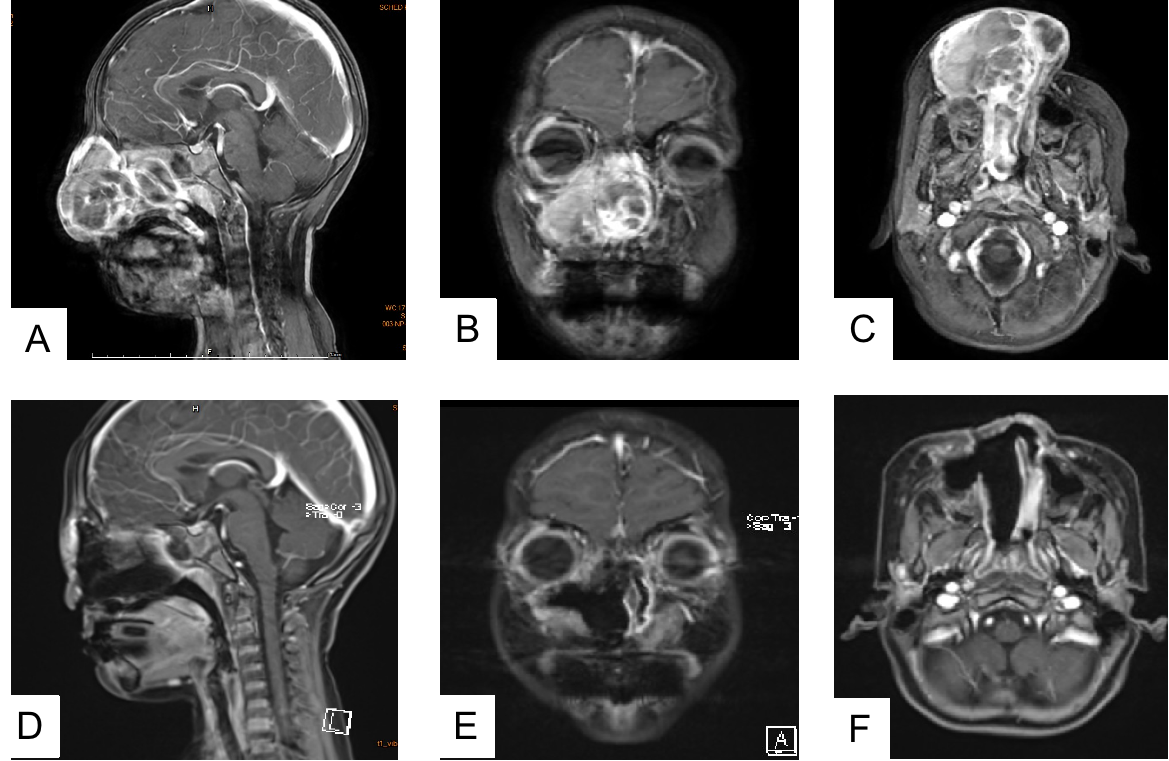

术前(A-C)术后(D-F)核磁共振影像对比

此时,肿瘤已广泛侵犯鼻腔、鼻窦、鼻咽及周边骨质,手术风险极高。文卫平教授组织了涵盖鼻专科、医学影像科、病理科、口腔颌面外科、神经外科、介入科、儿科、肿瘤科在内的八大学科多学科会诊,共同制定了“毫米级”的精密手术方案。团队先行通过介入技术精准栓塞肿瘤供血血管,次日,文卫平教授团队通过精细的鼻侧切开入路,以精细操作完整切除了肿瘤,并成功保护了周围重要功能结构。术后病理与影像学检查均证实肿瘤被彻底清除。